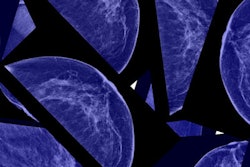

Despite significant increases in the number of cases of early-stage breast cancer detected since the 1970s, screening mammography has only marginally reduced the rate at which women present with advanced cancer, according to new research published in the November 22 issue of the New England Journal of Medicine.

In a study sure to add fuel to the already heated debate over the benefits and harms of screening mammography, researchers from Oregon Health & Science University concluded that their data raise "serious questions about the value of screening mammography" -- despite also finding that death rates dropped nearly 30% over this time period.

"Although it is not certain which women have been affected, [our study data suggest] that there is substantial overdiagnosis, accounting for nearly a third of all newly diagnosed breast cancers, and that screening is having, at best, only a small effect on the rate of death from breast cancer," wrote lead author Dr. Archie Bleyer and colleague Dr. H. Gilbert Welch (NEJM, November 22, 2012, Vol. 367:21, pp. 1998-2005).